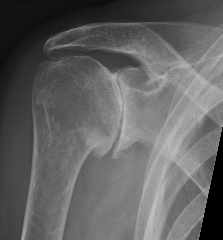

Samilson-Prieto

Grade 2 Grade 3

Grade 1: Osteophytes < 3 mm

Grade 2: Osteophytes 3 - 7 mm with slight narrowing GHJ

Grade 3: Ostephytes > 7 mm with GHJ narrowing and sclerosis